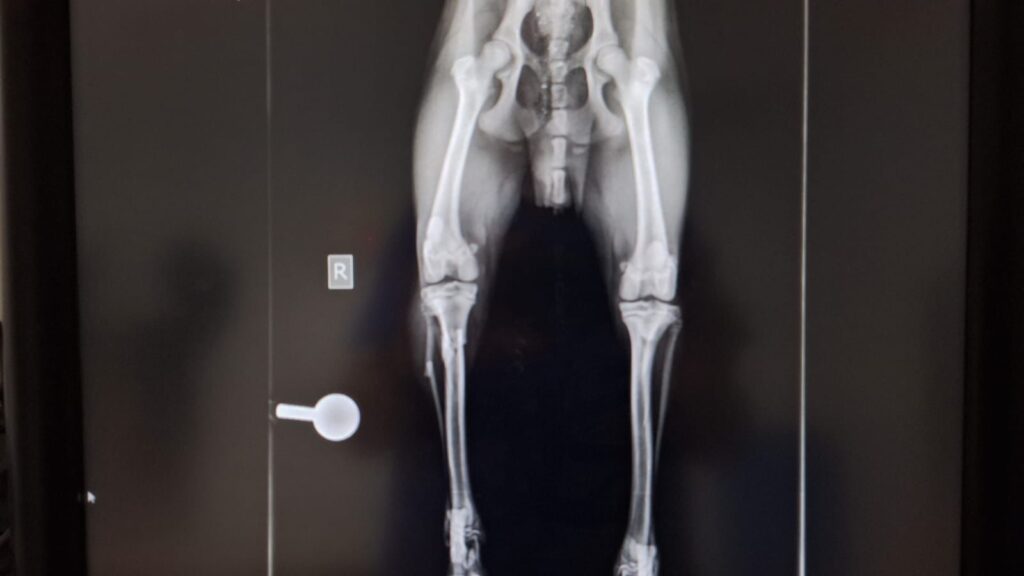

Kaiser braucht eure Hilfe

Kaiser wurde in Spanien überfahren und hat massive Verletzungen an 3 Beinen erlitten. Er wurde operiert und hat sich inzwischen auch schon recht gut erholt. Kaiser ist erst 9 Monate und ein sehr lieber und geduldiger Junge.